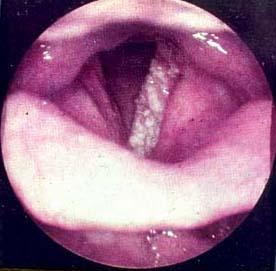

喉癌(carcinomaofthelarynx)是来源于喉粘膜上皮组织的恶性肿瘤,最常见的喉癌为喉鳞状细胞癌。多见于中老年男性。本癌的发生与吸烟、酗酒、长期吸入有害物质及乳头状瘤病毒感染等因素有关。喉癌发病率约占全身肿瘤的1~5%,在耳鼻喉科领域中仅次于鼻咽癌和鼻腔,鼻窦癌,居第三位。好发年龄为50~70岁。男性较女性多见。目前,以“特异性抗肿瘤免疫疗法”为带表的生物免疫治疗推行以来,使一大批肿瘤患者病情得到有效控制与减轻。